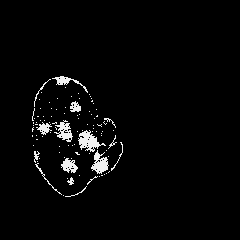

We introduce a neural network framework, utilizing adversarial learning to partition an image into two cuts, with one cut falling into a reference distribution provided by the user. This concept tackles the task of unsupervised anomaly segmentation, which has attracted increasing attention in recent years due to their broad applications in tasks with unlabelled data. This Adversarial-based Selective Cutting network (ASC-Net) bridges the two domains of cluster-based deep learning methods and adversarial-based anomaly/novelty detection algorithms. We evaluate this unsupervised learning model on BraTS brain tumor segmentation, LiTS liver lesion segmentation, and MS-SEG2015 segmentation tasks. Compared to existing methods like the AnoGAN family, our model demonstrates tremendous performance gains in unsupervised anomaly segmentation tasks. Although there is still room to further improve performance compared to supervised learning algorithms, the promising experimental results shed light on building an unsupervised learning algorithm using user-defined knowledge.